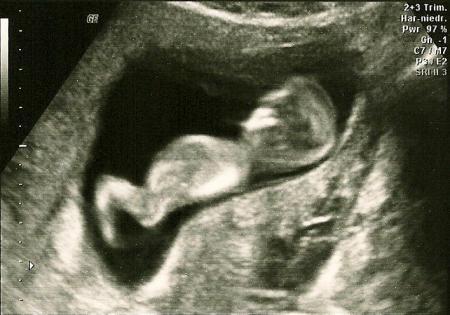

Hallo zusammen, ich wollte euch noch schnell von der NT-Messung heute berichten, bevor mein Kopf platzt. Ich habe heute tierische Kopfschmerzen. Werde wohl nachher eine Paracetamol nehmen, damit ich schlafen kann. Möglicherweise ist mein niedriger Blutdruck mit Schuld daran, keine Ahnung. Also, unsere kleine Maus lag gleich so, dass mein FA sofort die NT messen konnte. Das Ergebnis war mit 0,96 mm sehr gut (SSW 11+5). Nun muss ich noch das biochemische Ergebnis abwarten, erst dann erfahre ich natürlich das Gesamtrisiko. Trotzdem bin ich schonmal froh, dass die Nackenfalte unauffällig ist. Nachdem meine letzte Schwangerschaft bei der NT-Messung (unfreiwillig) endete, ist mir nun schon ein großer Stein vom Herzen gefallen. Ich hoffe, das Gesamtergebnis bekomme ich Anfang nächster Woche. LG

Hier noch die Bilder...